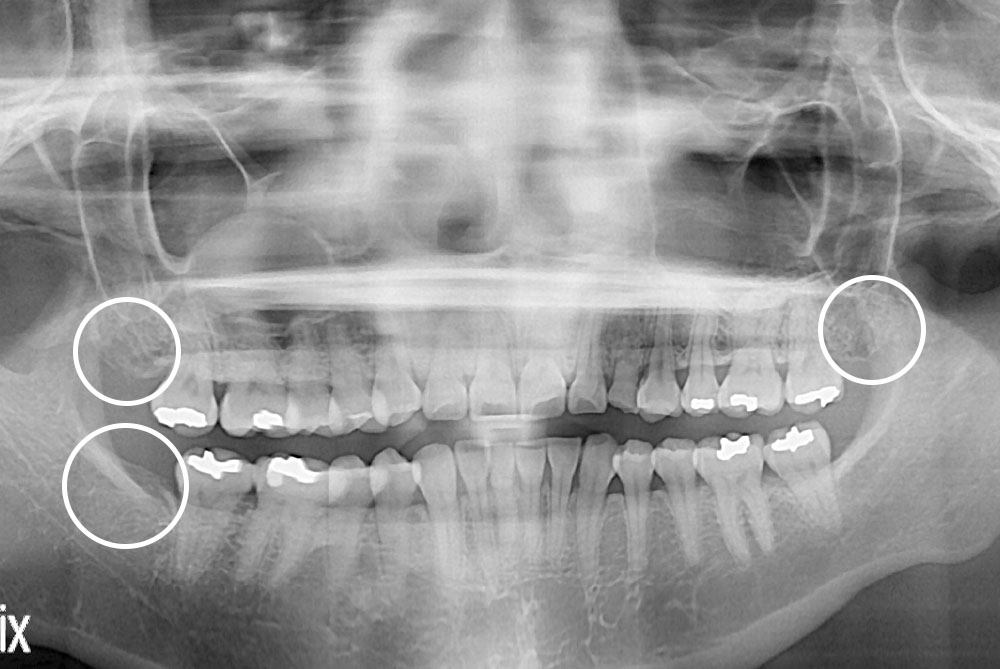

[사랑니] 매복 사랑니 발치

치료전 : 2018-07-17